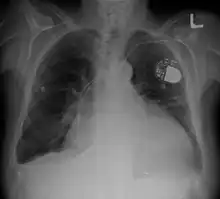

| Cardiomegaly on chest X-ray with a pacemaker | |

- Chest X-ray: X-ray images help to visualize the condition of the lungs and heart. If the heart is enlarged on an X-ray, other tests will usually be needed to find the cause. A useful measurement on X-ray is the cardio-thoracic ratio, which is the transverse diameter of the heart, compared with that of the thoracic cage.[24] These diameters are taken from PA chest x-rays using the widest point of the chest and measuring as far as the lung pleura, rather than lateral skin margins. If the ratio is greater than 50%, pathology is suspected.[25] The measurement was first proposed in 1919 to screen military recruits. A newer approach to using these x-rays for evaluating heart health takes the ratio of heart area to chest area and has been called the two-dimensional cardiothoracic ratio.[26]

- Pacemaker: Coordinates contractions between ventricles. In people at risk of arrhythmias, drug therapy or an implantable cardioverter-defibrillator (ICD).